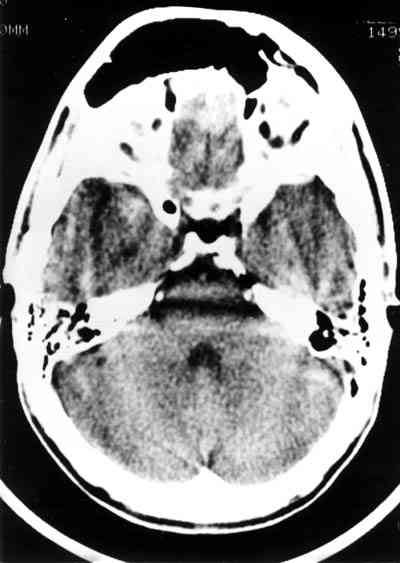

Figura 4

PROYECCIÓN AXIAL DE TAC CRANEAL MOSTRANDO LA CAVIDAD FRONTAL DERECHA HIPERNEUMATIZADA HACE 7 AÑOS Y PREVIA LA INTERVENCIÓN.